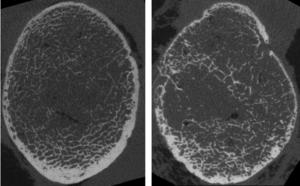

Exploring photon-counting CT